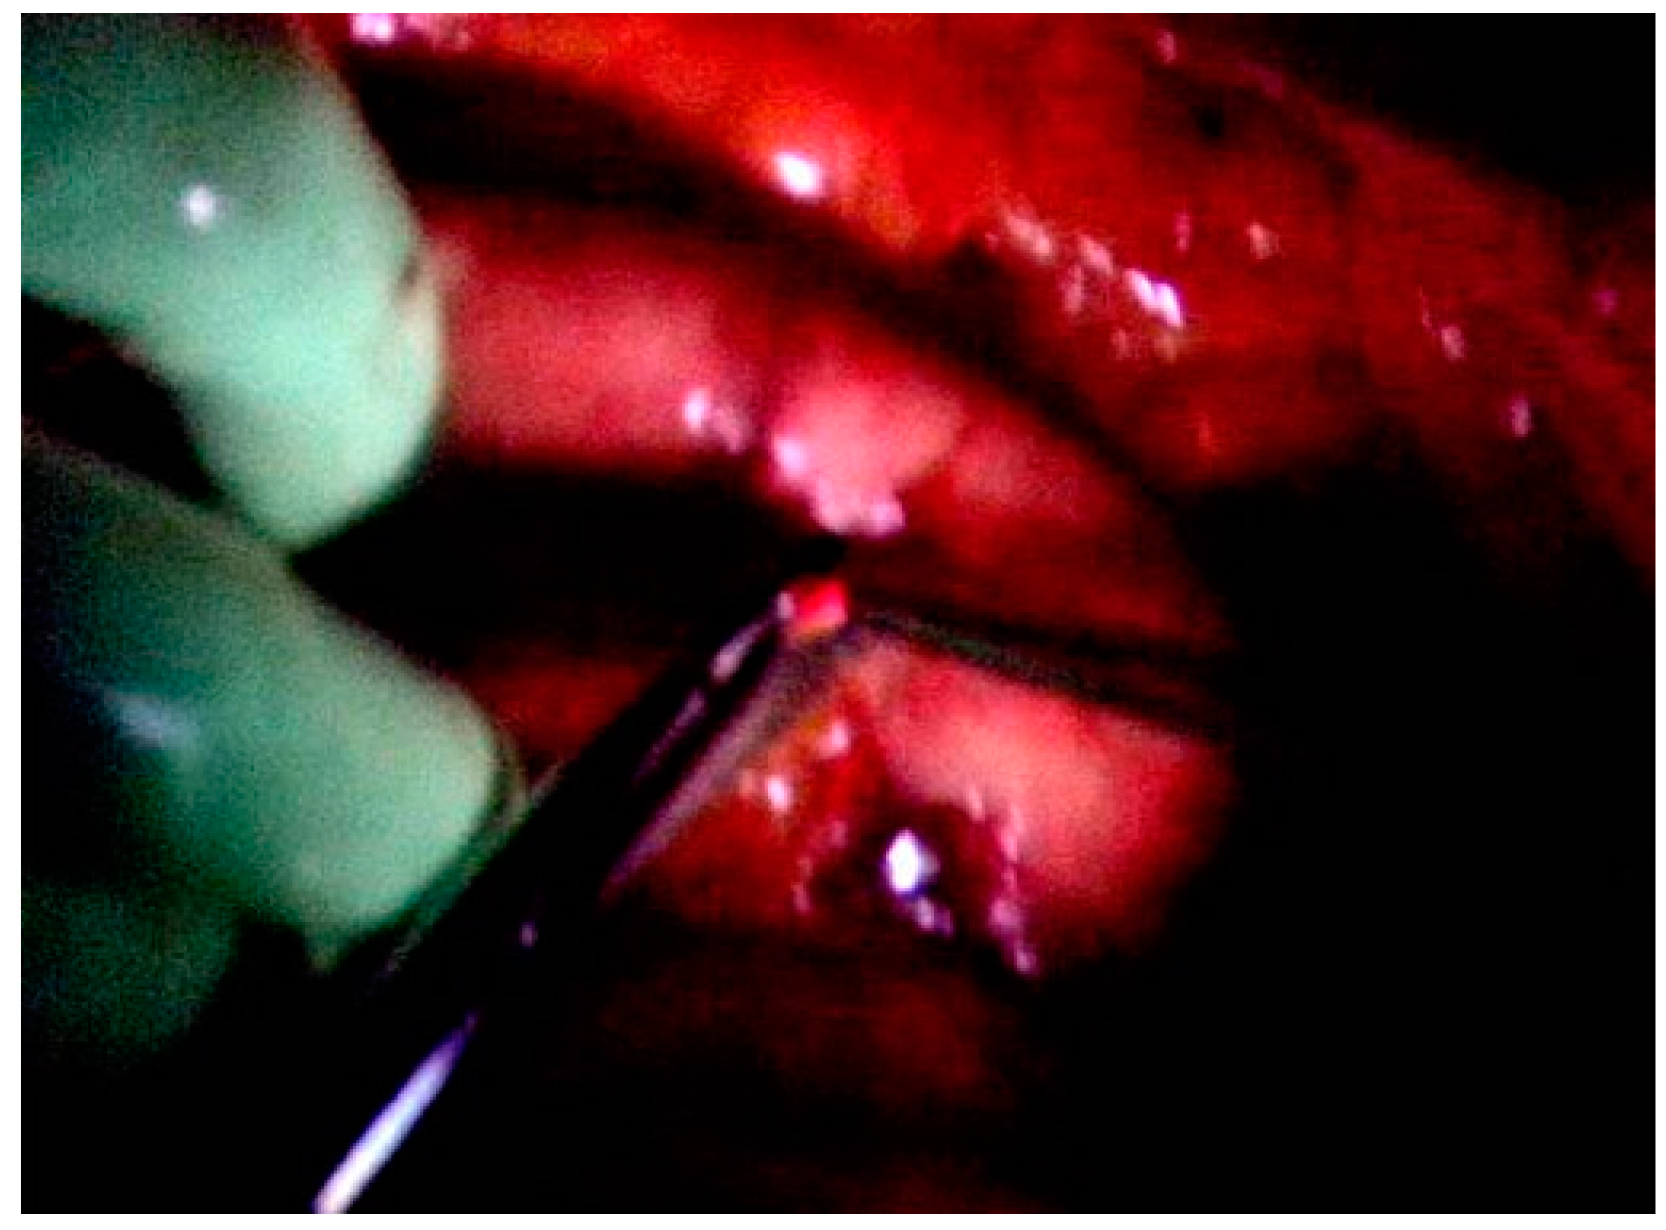

4. Clinical Application of ALA PDD to Detect Peritoneal Metastasis: ALA-Guided Cytoreductive Surgery

4.1. Methods of ALA PDD and ALA-Guided Cytoreductive Surgery

- Liu, Y.; Endo, Y.; Fujita, T.; Ishibashi, H.; Nishioka, T.; Canbay, E.; Li, Y.; Ogura, S.; Yonemura, Y. Cytoreductive surgery under aminolevulinic acid-mediated photodynamic diagnosis plus hyperthermici ntraperitoneal chemotherapy in patients with peritoneal carcinomatosis from ovarian cancer and primary peritoneal carcinoma: Results of a phase I trial. Ann. Surg. Oncol. 2014, 24, 4256–4262. [Google Scholar] [CrossRef]

- Canbay, E.; Ishibashi, H.; Sako, S.; Kitai, T.; Nishino, E.; Hirano, M.; Mizumoto, A.; Endo, Y.; Ogura, S.; Yonemura, Y. Photodynamic detection and management of intraperitoneal spreading of primary peritoneal papillary serous carcinoma in a man: A case report. Surg. Today 2014, 44, 373–377. [Google Scholar] [CrossRef] [PubMed]